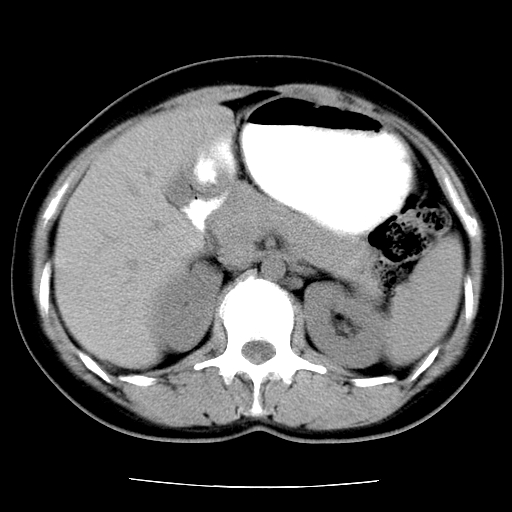

标题: CT16892:女40Y,急性阑尾住院!

女40y,急性阑尾住院!术前发现请会诊!

考虑门静脉瘤样扩张可能,建议增强扫描

胰头假性囊肿也有可能,建议增强

病灶位于门静脉的位置 ,有层面显示血管夹层样改变 ,考虑是门静脉瘤样病变1

病灶位于门静脉的位置 ,有层面显示血管夹层样改变 ,考虑是门静脉瘤样病变,建议进一步增强ct检查。

肝门区囊性占位,壁有钙化,考虑良性。来源难定。